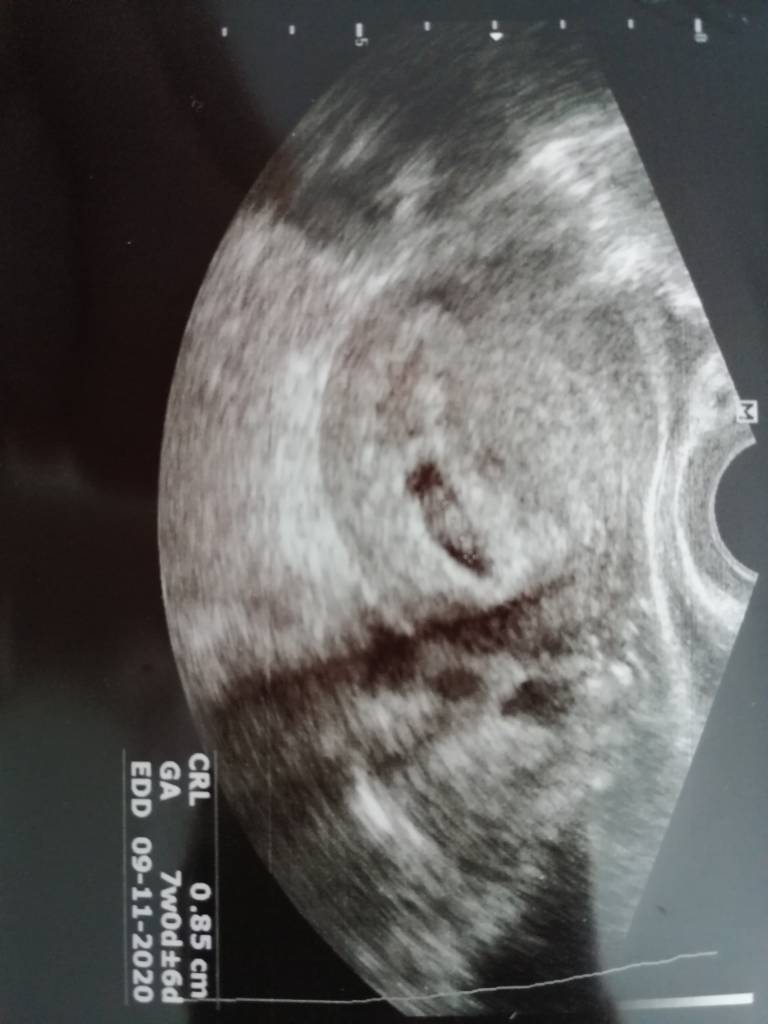

Dzidziuś jest i serduszko też puka, kamień z serca ale tak słabo się dziś czułam rano, że myślałam że zemdleje, tz mnie zawiózł autem bo bylo mi tak słabo i miałam jakieś odruchy wymiotne... Wg usg 7t +0 i dzidziuś jest taki jak trzeba [emoji6]Zobacz załącznik 1095483